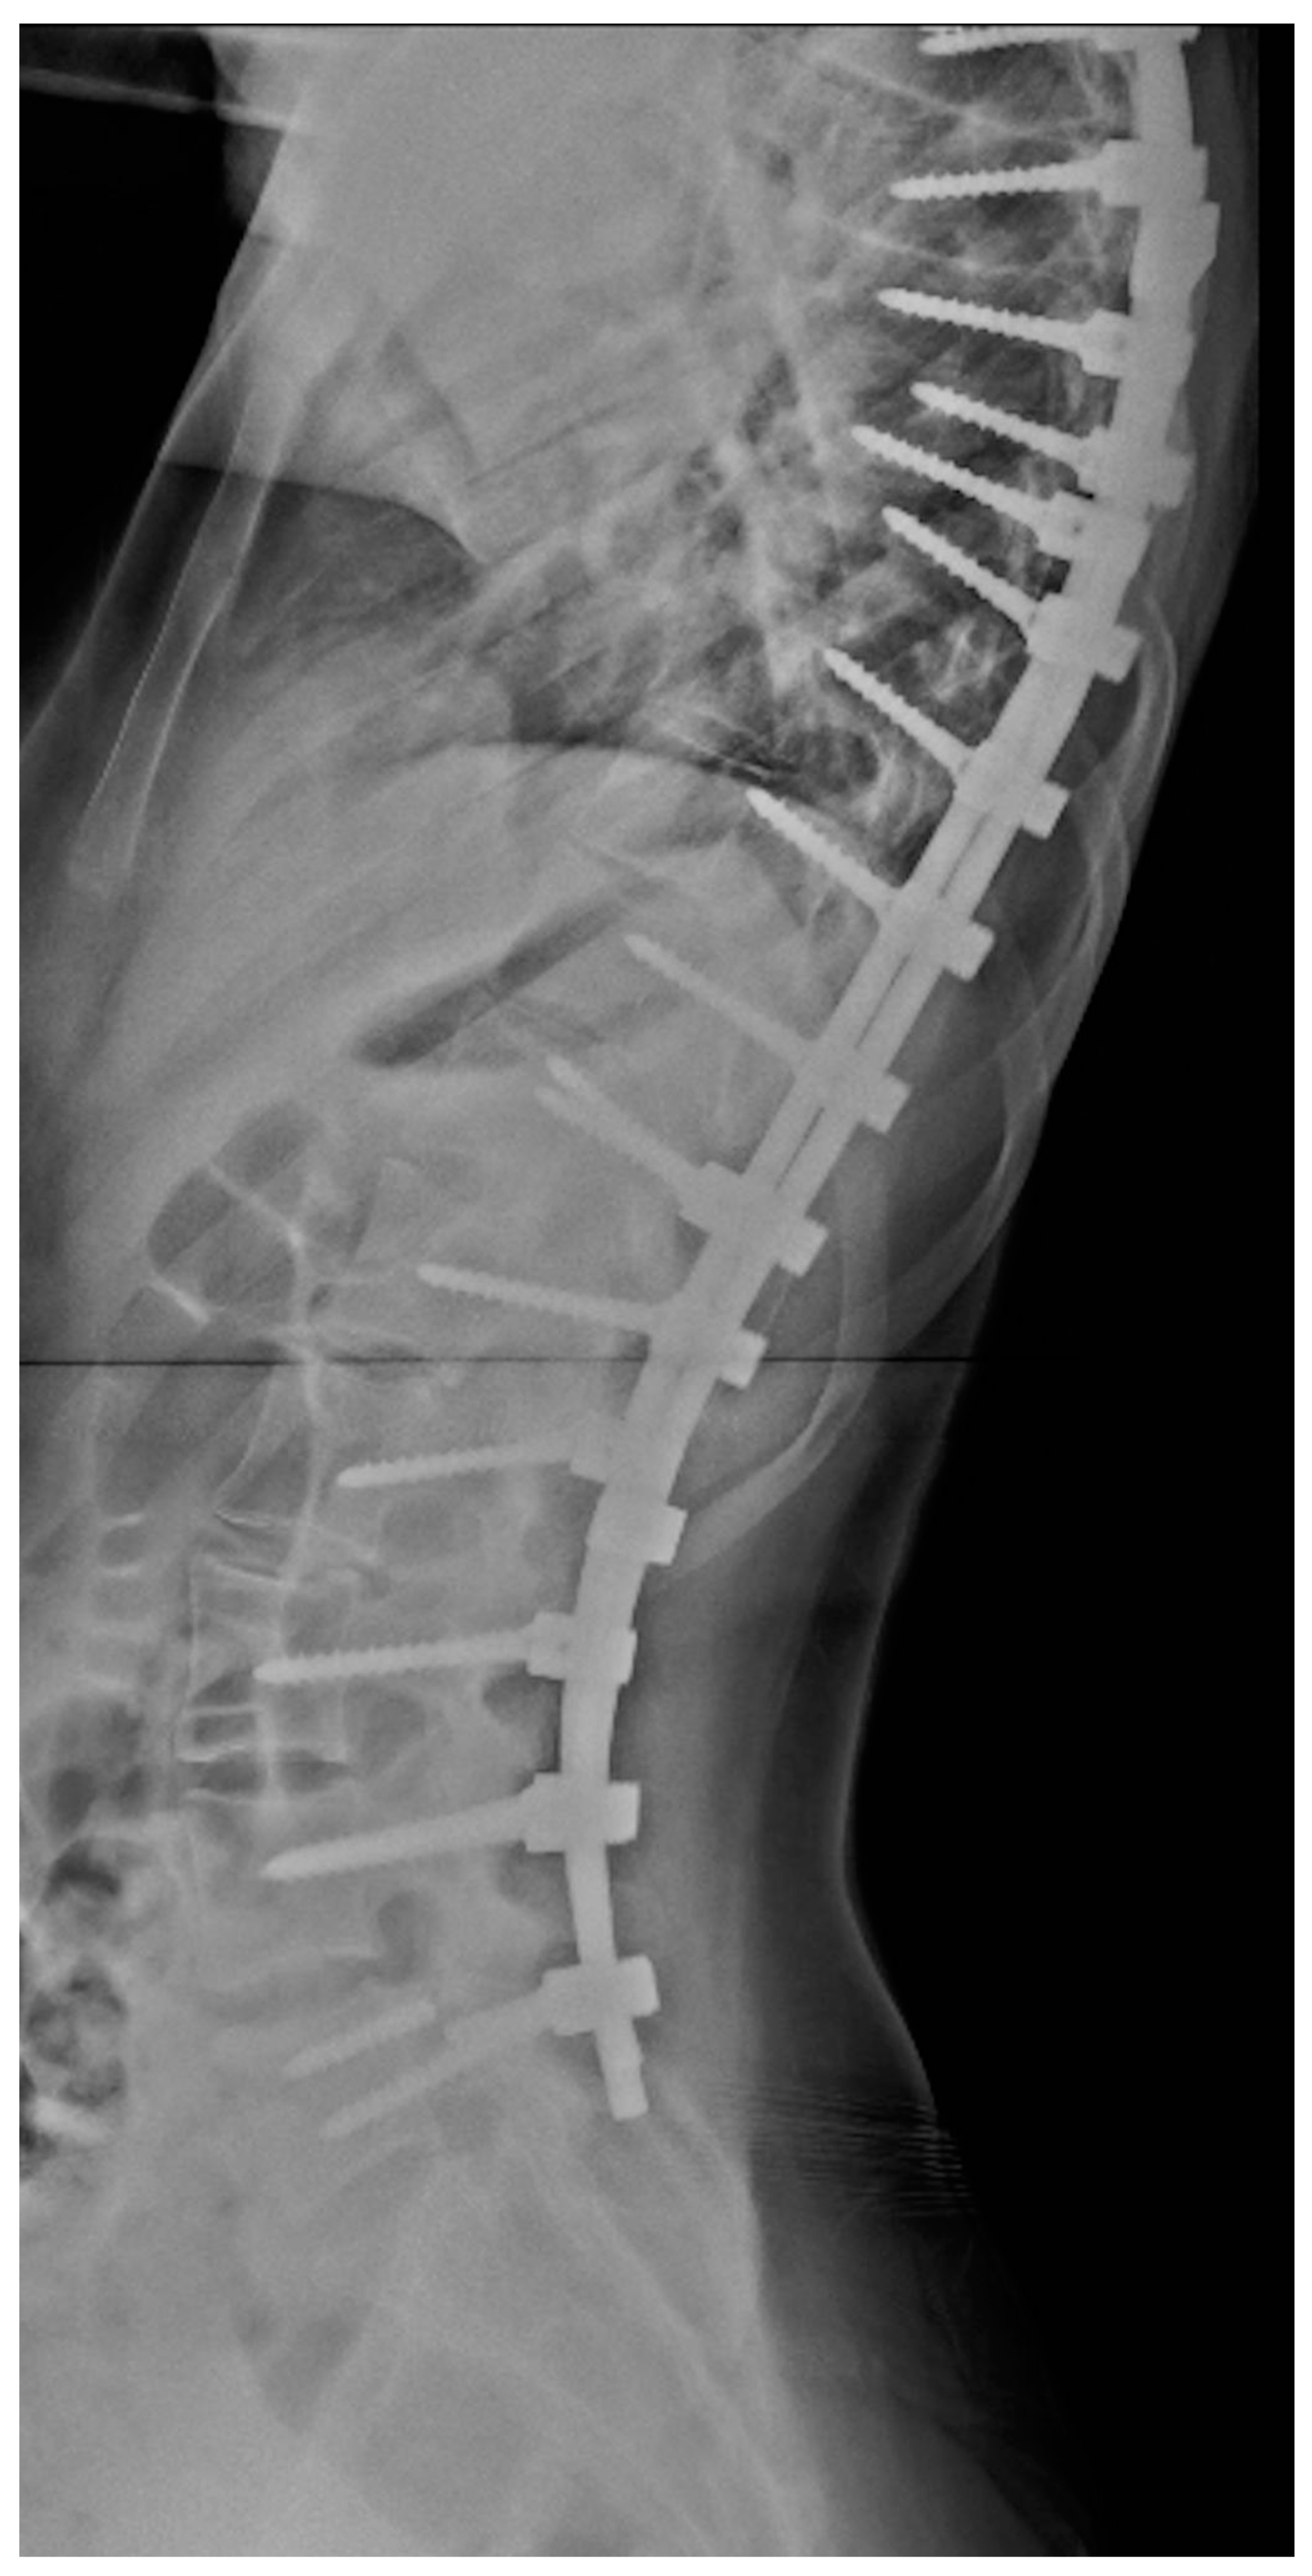

The probability of material failure was 2.73% in the first year after surgery and 10.1% over four years (example, Figure 1). The average time from surgery to diagnosis of the complication was 309 days. Of the 330 patients included in the study, only 21 (6.36%) had implant failure, and of those, only 9 required revision surgery. This fact demonstrates that most patients, even those with mechanical failure, did not need revision surgery due to the absence of clinical complaints or neurological dysfunction.

Figure 1.

Lateral X-ray showing pedicle screw breakage at L5.